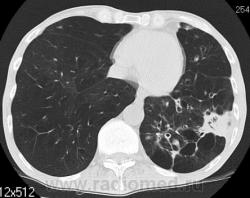

На фоне консолидации полость без содержимого. Может быть всё что угодно, что сопровождается деструкцией. Нужны ещё томограммы в лёгочном окне.

Изображения выставлены все. Ваше мнение уважаемые коллеги?

Туберкулёз.

Туберкулёз?

Это КТ 2-летней давности и попало оно мне в руки, после недавнего прохождения контроля пациентом, когда мы стали перед вопросом о специфическом / не специфическом процессе.

Тогда, пациента 2 месяца лечили от пневмонии, лечили интенсивности, стационарно, в серьёзном учреждении.

Нет опыта работы на цифровых аппаратах: дефекты правого нижнего лёгочного поля объясняются артефактами?

Предположу аспергиллез